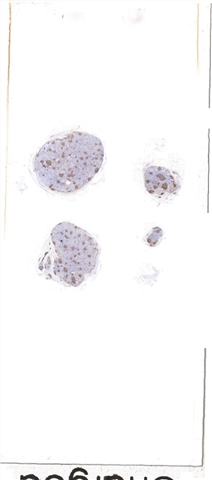

| 大体所见: | 颈部淋巴结4枚,直径0.2cm,0.4cm,0.8cm和1cm。 |